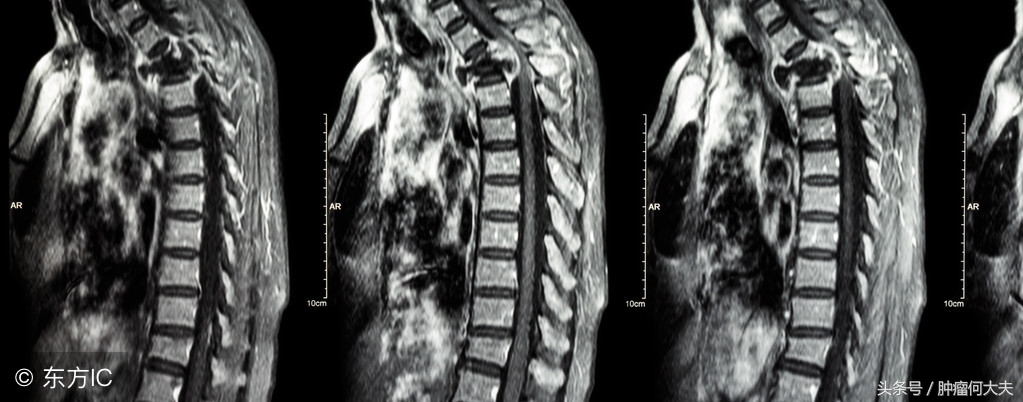

其次,怀疑骨转移要做这些特殊检查:①X线平片检查,表现为骨破坏和骨质修复共存。乳腺癌、肺癌、甲状腺癌和黑色素瘤主要表现为骨破坏、塌陷、骨折。前列腺癌表现为骨增生,成为成骨性改变。②放射性核素骨扫描,骨扫描是最常用和最敏感的方法。可比X线早发现骨转移3~6个月。③CT和MRI,可显示骨破坏和软组织肿块病灶。MRI是肿瘤脊髓压迫症的首选检查方法。